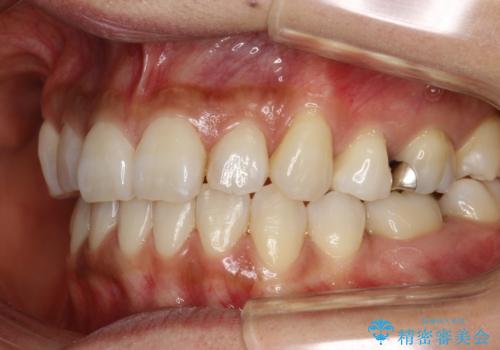

ハーフリンガル抜歯矯正 八重歯を改善する

- 小臼歯4本抜歯によるハーフリンガル・ワイヤー矯正を計画した。

シビアな八重歯がきれいに歯列にはいることにより、笑った時の印象などもかなり大きく変わります。